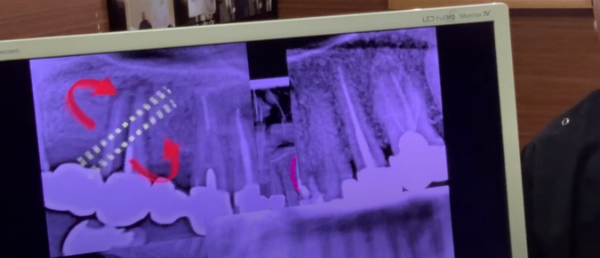

反対側です。

根っこがありません。

何らかの原因で

抜くことになったわけですけれども

残っている歯を繋いで

橋わたしをして

そして

ブリッジ治療をしたと

そうすると

歯がなくなったのに

歯が入りましたから

みなさま

治ったと思われます。

ところが

考えてみればですね

非常に単純なのですが

元々は柱の本数

これだけあったわけですね

ブリッジ治療はして

歯は入ったけれども

柱の本数

少ないですよね

ということは

以前と同じ噛み方をしたらどうなるのか?

3本で柱を例えば支えているのであれば

3本の柱でも耐えられる強度以上の力がもし

かかったならば

当然柱は耐えきれなく

まき割りのような力がかかって

真っ二つにパーンと割れてきてしまうんですね。